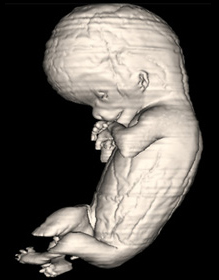

Source: The Virtual Human Embryo.